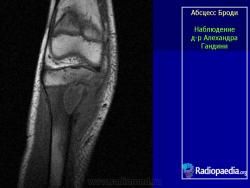

Рентгенологически обнаруживают полость с чёткими склерозированными контурами, при обострении периостальные наслоения, остеосклероз.

Особенностью гнойника Броди является локализация в губчатом костном веществе, причем практически почти никогда не поражаются мелкие или плоские кости, а исключительно большие трубчатые кости, а именно метафизарные концы. На первом месте по частоте заболевания стоят суставные концы костей, образующих коленный, голеностопный и локтевой суставы. Самым типичным и излюбленным местом локализации гнойника является большеберцовая кость, на долю которой выпадает 80% всех случаев, причем проксимальный метафиз поражается чаще, чем дистальный. Гнойник предпочтительно располагается поверхностно, под корковым слоем кости.

Характерен для абсцесса Броди значительный остеосклероз губчатого вещества, окружающего полость, и лишь очень редко гнойник лежит среди нормальной спонгиозной ткани. На поверхности кости периостальные наслоения очень незначительны, так что если вообще имеется цилиндрическое или, скорее, веретенообразное утолщение метафиза на уровне гнойника, то только в самой умеренной степени. Как правило, секвестрации не бывает. До прорыва наружу или в полость соседнего сустава, несмотря на его близость, дело доходит лишь в редчайших случаях.

Рентгенологическое исследование имеет решающее диагностическое значение. Все детали патологоанатомической картины абсцесса Броди передаются в точности и на рентгеновских снимках (рис. 207 и 208). Изолированная, правильной округлой формы полость, без секвестра, с резко ограниченными гладкими внутренними контурами, расположенная среди склерозированного губчатого вещества, на типичном месте — в метафизарном конце большой трубчатой кости, слегка утолщенной благодаря периостальным наслоениям, — эта рентгенологическая картина при поддержке клинических симптомов разрешает диагностическую задачу. При этом следует учесть, что между, так сказать, классическим типичным абсцессом Броди и другими формами хронического остеомиелита бывают и переходные формы — и по местоположению, размерам, форме, характеру реактивных изменений в окружности, секвестрации и т. д. Это ведь в природе вещей: классификация показывает всегда несколько условно типичное, жизнь преподносит многообразие, не укладывающееся в строгую жесткую схему. Никоим образом не следует злоупотреблять диагнозом абсцесса Броди и ставить его расширительно, чуть ли не во всех случаях более или менее ясно выраженной полости при обычном хроническом остеомиелите: абсцесс Броди — это совершенно определенное клинико-рентгено-анатомическое понятие, это четкая нозологическая единица, и диагноз оправдан лишь в тех случаях, когда рентгенологическая картина удовлетворяет всем вышеперечисленным критериям.